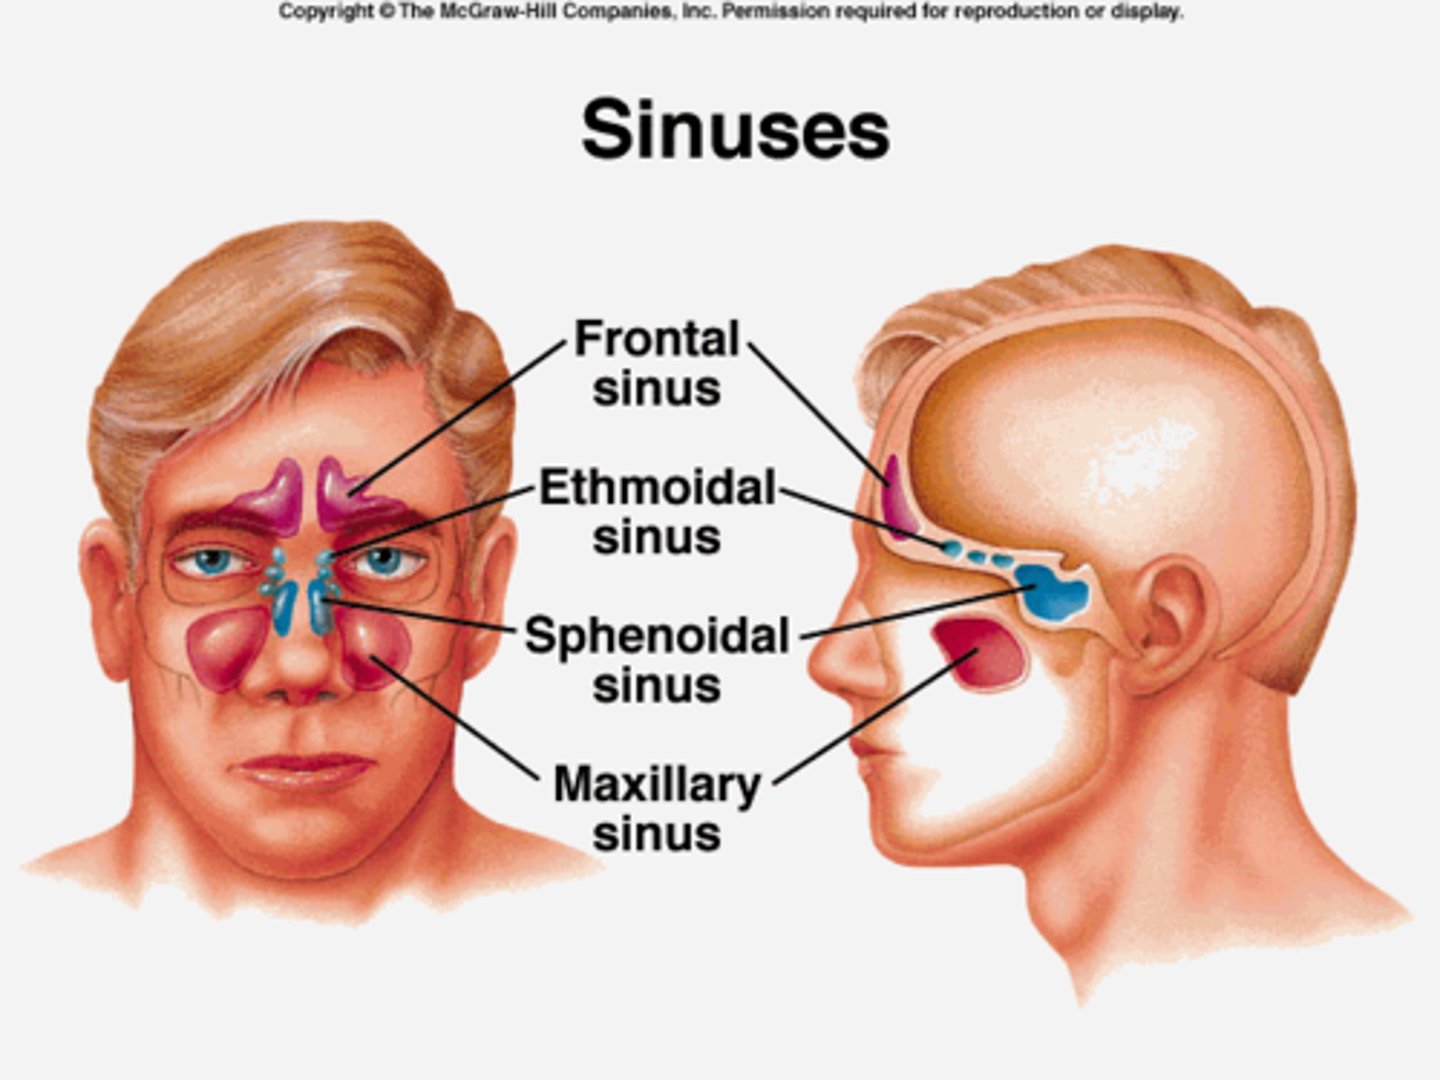

What are sinuses?

air pockets in the bones of the skull (pneumatized)

What makes sinuses vulnerable to infection?

They are continuous with the nasal cavity

What are the paranasal sinuses?

frontal, sphenoid, ethmoid, maxillary

What is the purpose of having sinuses?

1. reduce weight of skull

2. humidify and heat inhaled air

3. increase resonance of speech

4. protect vital structures during facial trauma